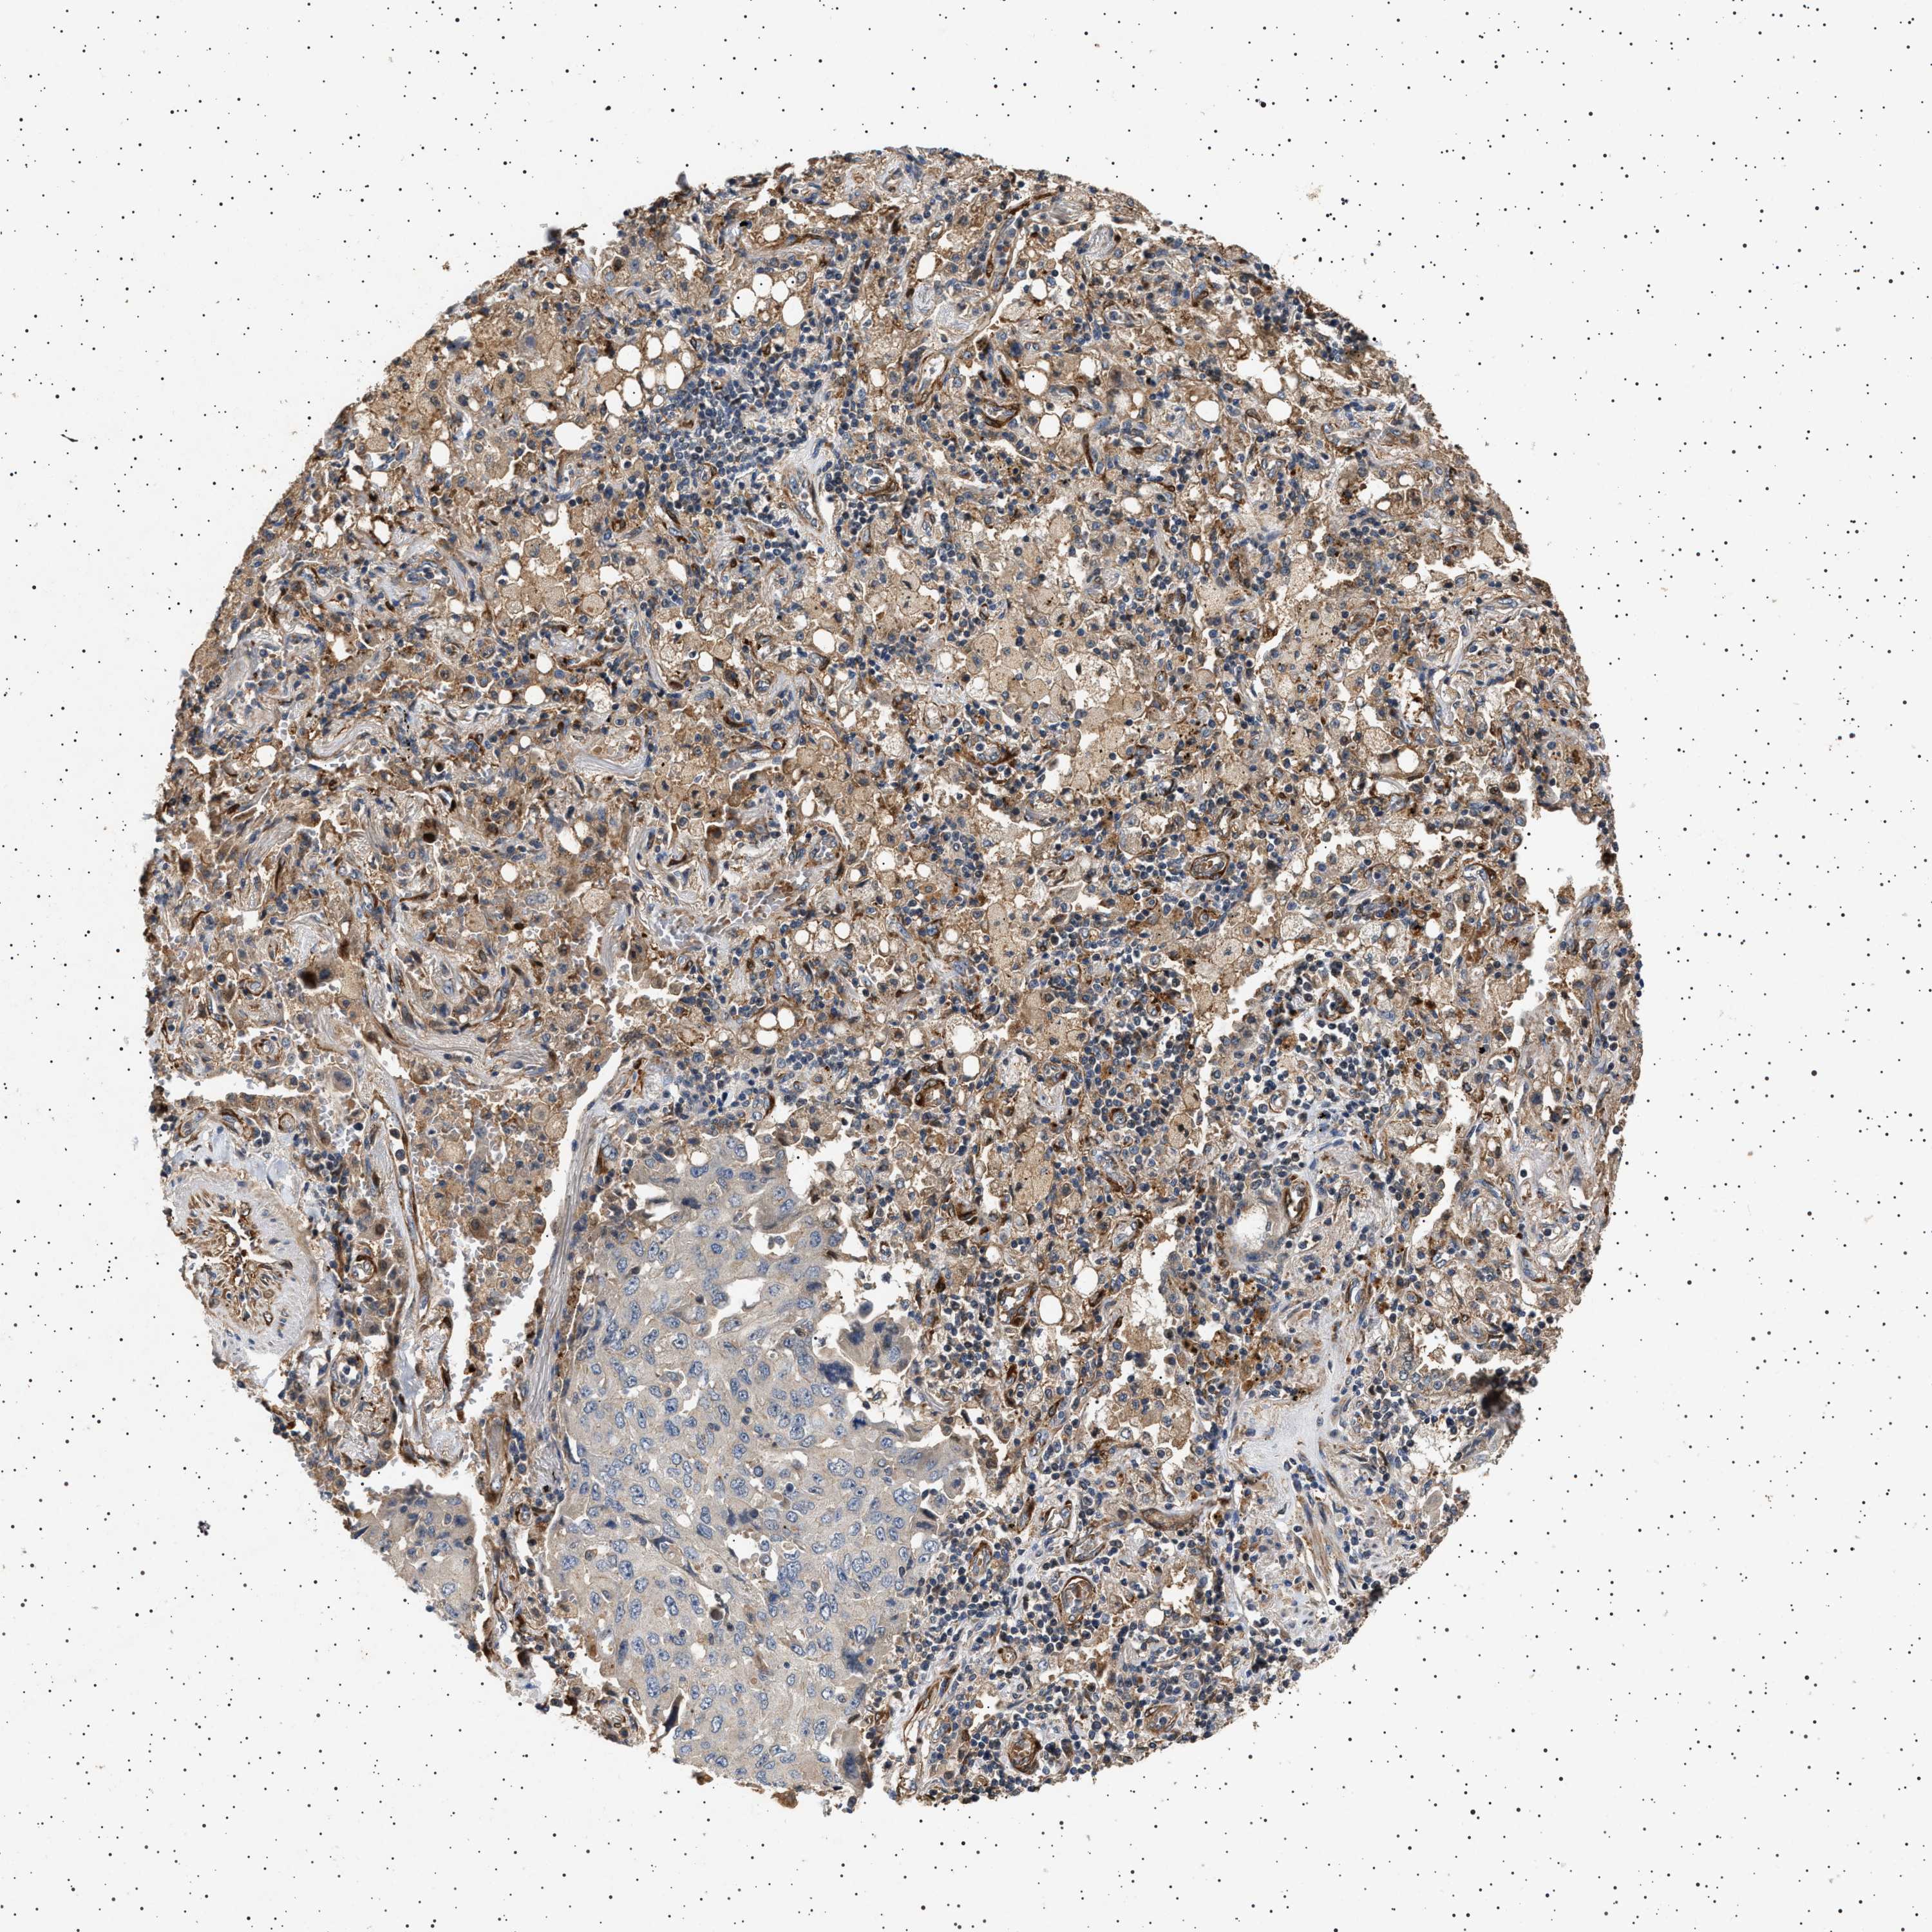

CANCER LUNG CANCER Show tissue menu

Lung cancer

Human cancer